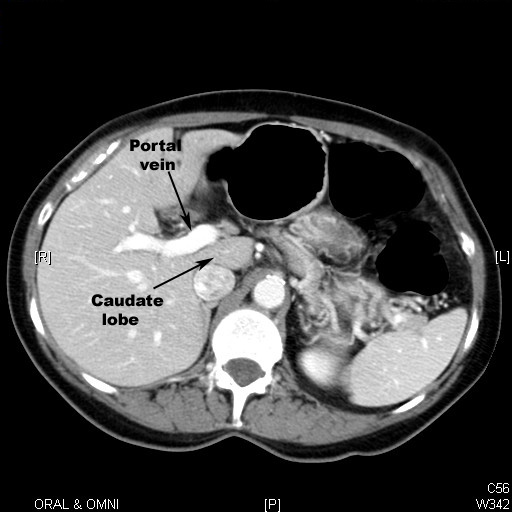

Normal Liver

• It is divided into four lobes of unequal size and shape.

• It is important to understand the complex blood flow (hepatic and portal systems) through the liver.

• Parenchyma (Reticulo endothelial cells)  enhances with contrast uniformly with portal vein and hepatic artery branches seen through it.

• In the superior slices we can see hepatic veins draining into inferior venacava.

• It is of same density as spleen.

• Normal biliary ducts are not seen. They are seen only when they are dilated.